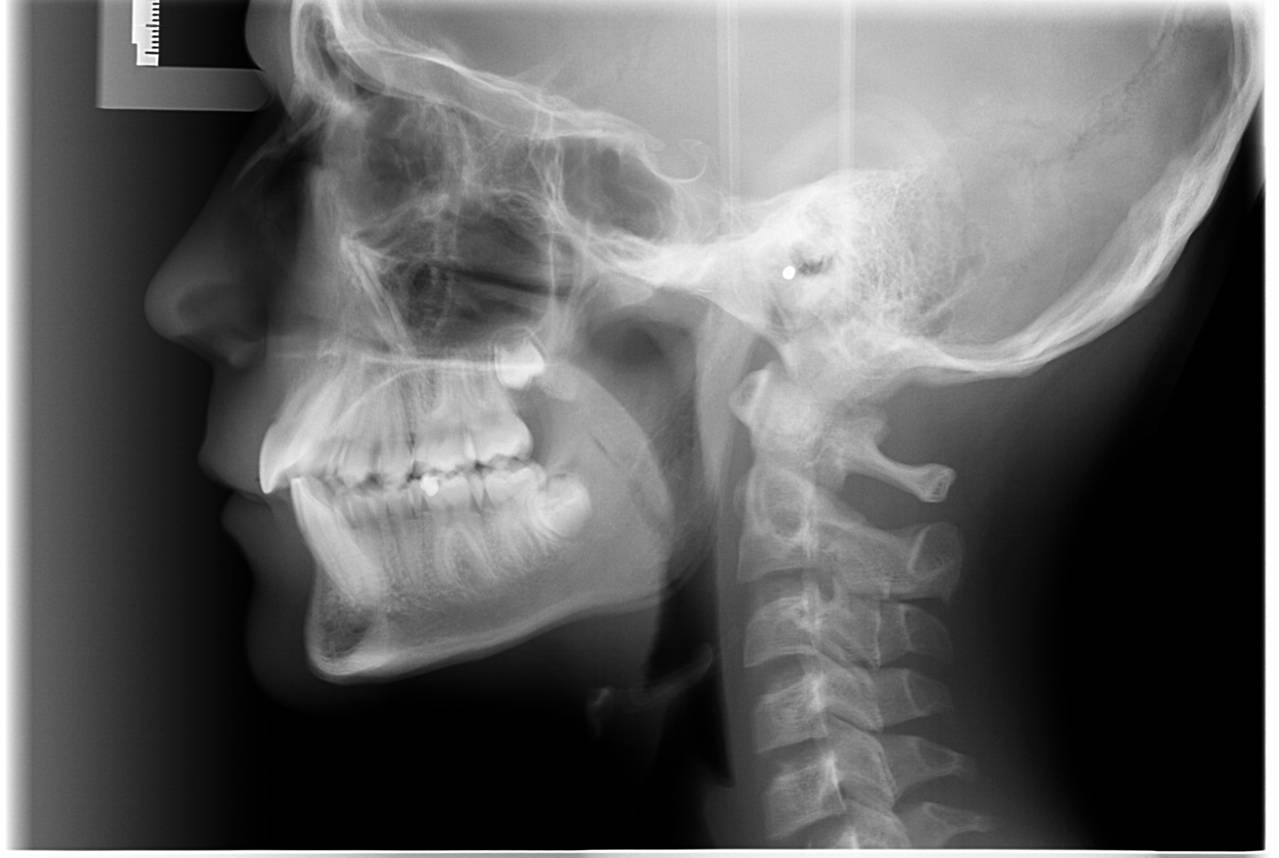

- Vi tager røntgenbilleder af tænder, kæber og hoved.

Når du har takket ja til tandreguleringsbehandling, har du og dine forældre også givet accept til, at vi tager et røntgenbillede ca. hver 6. måned.

Vi tager røntgenbilleder for at kontrollere, om rødderne kan klare belastningen med faste bøjler.

Der tages desuden fotos af tænderne og ansigtet samt røntgenbilleder.